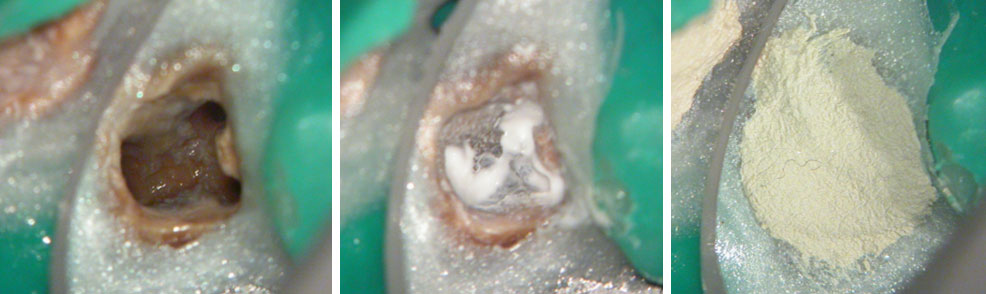

Red arrow shows calcification covering the MB2. Removal of this calcification with ultrasonics reveals the missed MB2(yellow arrow)

5 canals cleaned, shaped and obturated after 10 days of calcium hydroxide. MB1 and MB2 had seperate portals of exit. DB2 merged intoDB1. Palatal two portals of exit.